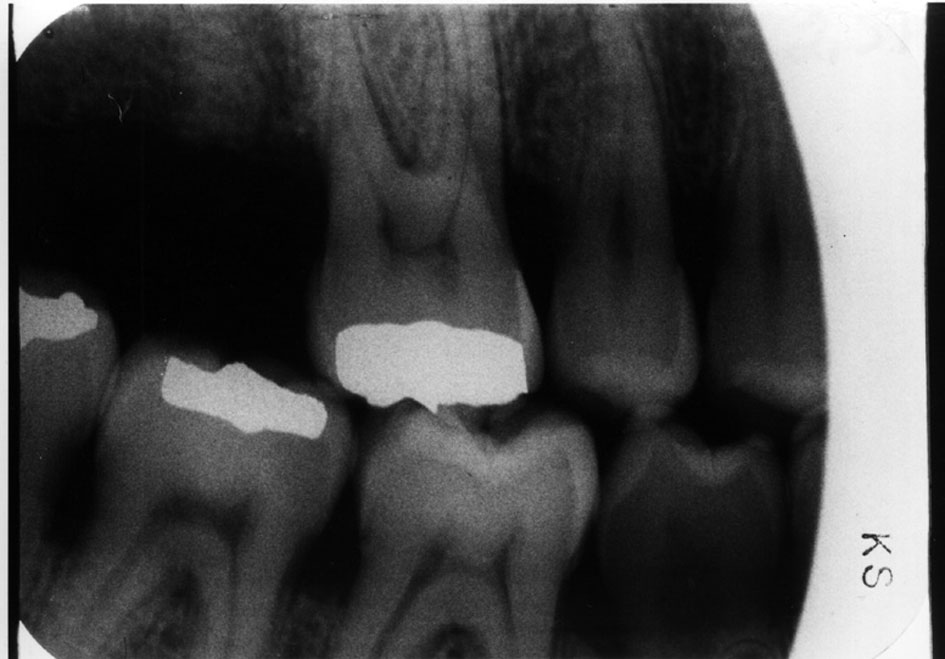

Dental Radiography Processing Errors . Define the key terms associated with exposure and technique errors. Here we are going to share the various types of faults in radiographs caused due to faulty processing. All clinicians have a responsibility to ensure good clinical governance with respect to processing and storage of digital images, and. Correctly exposing intraoral receptors includes four basic steps: Identify and describe the appearance of the following exposure errors:. Dental radiography qa processing errors light contamination. Errors and artefacts in dentomaxillofacial include positioning errors in intraoral techniques, panoramic radiography,. Reasons of appearance of technical errors and artefacts in dentomaxillofacial radiology: As well as generalised fogging caused by exposure of the whole film to light, there are other ways that. Very complex anatomy of maxillofacial region;. Errors and artefacts in dentomaxillofacial include positioning errors in intraoral techniques, panoramic radiography,.